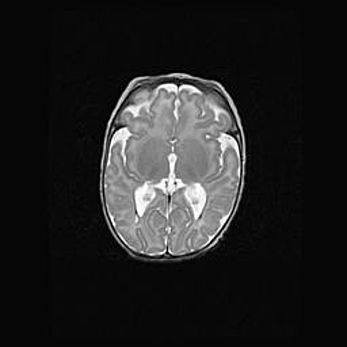

Множественные кисты обоих полушарий головного мозга, наибольшая из них в правой затылочной области. Ассиметричная атрофическая гидроцефалия.

Возраст: 7 месяцев

Вес: 5660 г

Пол: мужской

Окружность головы: 41,5 см

Срок гестации: 28-29 недель

Кисты головного мозга развиваются в результате многоочаговых некрозов вещества мозга и возникают вследствие перенесенной перинатальной инфекции, менингитов, энцефалитов, асфиксии, родовой травмы, расстройств мозгового кровообращения различного генеза. Образованию кист в веществе головного мозга плодов и новорожденных способствуют такие факторы, как высокое содержание в нем воды, недостаточная (или отсутствие) миелинизация и слабая астроглиальная реакция на повреждение.

Кисты могут сочетаться с гидроцефалией и другими поражениями головного мозга.